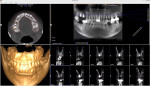

To confirm which sinus space the foreign body was in (ie, SCS or SMS), three radiographs were taken at different intervals. The first was taken with the patient in a supine position, and two additional radiographs were taken with the patient in an upright position after walking around to determine if the foreign body was in motion. All three radiographs revealed that the aberrant foreign body remained in a static location and was entrapped within the space between the sinus membrane and bony wall of the maxilla.CBCT analysis was used in this case since the object was in the SMS and was immobile.

Subsequently, two dental implants (OsseoFuse Sinus, OsseoFuse, osseofuse.com) were immediately placed into the maxillary right posterior arch according to the Hydraulic Sinus Condensing (HSC™) technique (Dental Implant Institute, dentalofficeslasvegas.com). This served to improve implant osseointegration, minimize the invasiveness of the sinus lift protocol, and prevent sinus membrane perforation.15-17,22 A postoperative CBCT was taken to confirm implant placement stability (Figure 13) and ensure that the sinus area was disease-free.